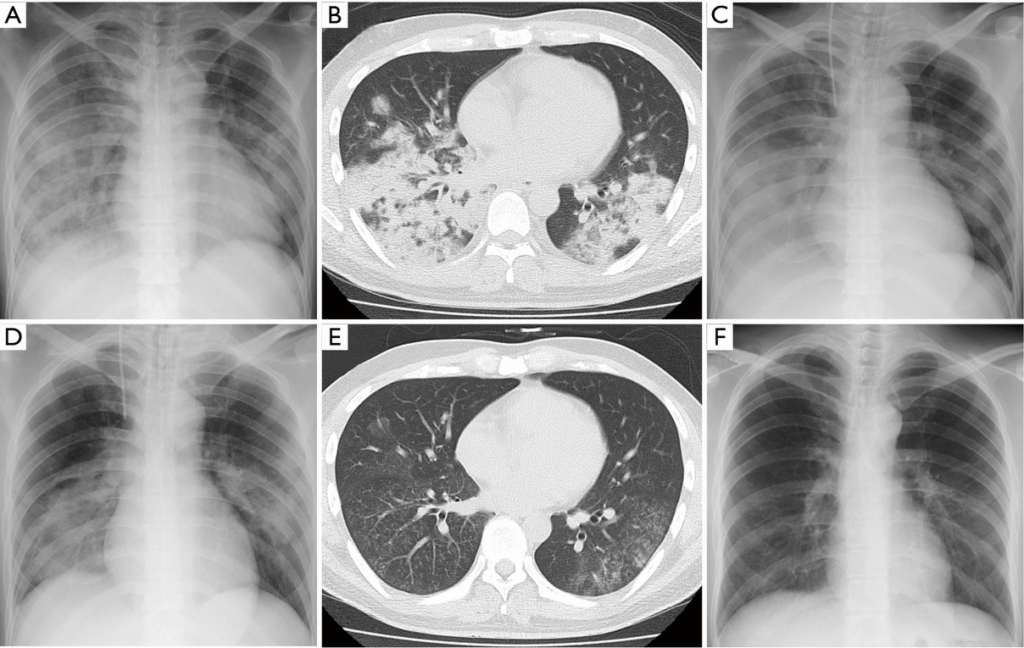

Даже при проведении рентгенографии органов грудной клетки нельзя выявить симптомы, характерные именно для микоплазменного воспаления лёгочной ткани. Врач увидит лишь усиление лёгочного рисунка и признаки воспаления, к которым могут привести любые другие инфекции.

Для диагностики микоплазменной пневмонии проводится рентген, где должно быть видно усиление легочного рисунка, а также мелкоочаговые тени в нижних отделах легких. Помимо этого необходимо серологическое исследование крови, которое показывает наличие или отсутствие специфических иммуноглобулинов к возбудителю.

При постановке диагноза микоплазменной пневмонии учитываются данные клинической картины, рентгенографии и КТ легких, серологического и ПЦР-исследований. Установление этиологии на первой неделе заболевания затруднено из-за первоначальной невыраженности физикальных проявлений. Рано отмечается гиперемия задней стенки глотки, гипертрофия миндалин, постепенно может появиться очаговое ослабленное везикулярное дыхание, крепитация, редкие средне- и мелкопузырчатые хрипы, укорочение перкуторного звука. Для микоплазменной пневмонии типично присутствие внелегочной симптоматики.

На рентгенограмме легких заметно двустороннее усиление легочного рисунка с типичными для пневмонии неоднородными, нечеткими очаговыми инфильтратами в нижних сегментах, в 50% случаев – интерстициальные изменения, перибронхиальная и периваскулярная инфильтрация. Обширная лобарная инфильтрация отмечается редко.